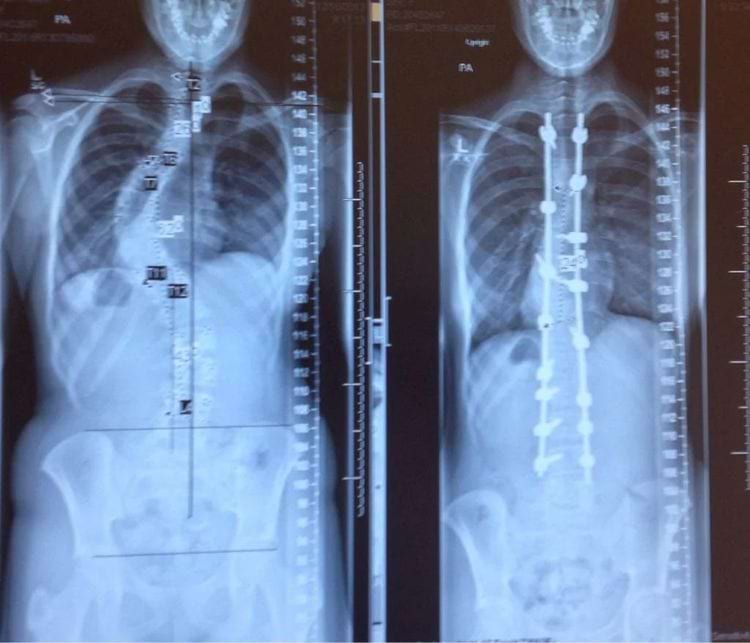

«Мои рентгеновские снимки до и после лечения сколиоза»